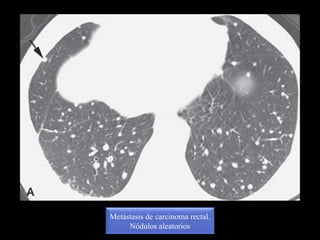

Nodulos aleatorios

Metástasis de carcinoma rectal.

Nódulos aleatorios